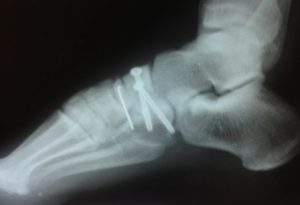

Когда отломки кости смещены, нужна репозиция под внутрикостным обезболиванием или внутривенным наркозом. Вывих и перелом ладьевидной кости требует установки специальной конструкции Черкес-заде, когда одна спица проводится через пяточную кость, а другая проходит через плюсневые кости (их головки).

В тяжелых случаях выполняется оперативное лечение, после которого необходимо ношение гипсовой повязки не меньше месяца. Для контроля в динамике делают рентгеновские снимки. Необходимо понимать, что все костные структуры в ступне взаимосвязаны, поэтому нужно полностью восстановить место перелома.